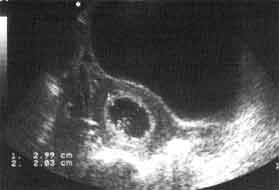

Ovalaire > 8 semaines